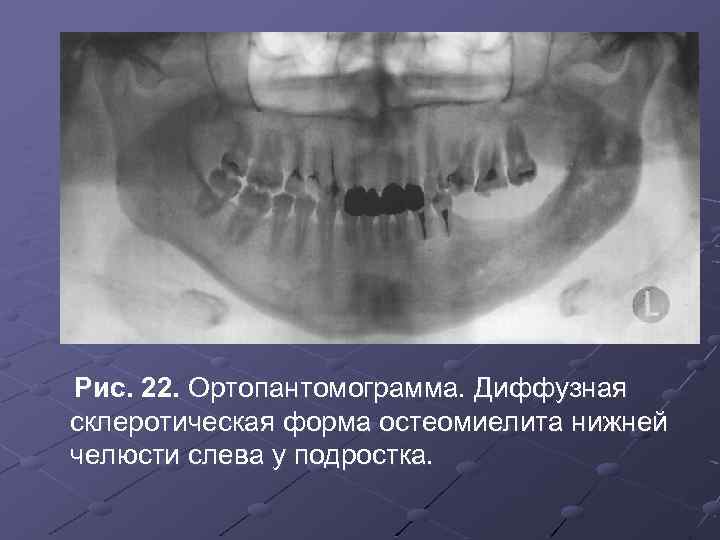

Рентгеновские снимки посттравматического остеомиелита челюсти: Медицинские случаи

Раздел: Образы вокруг